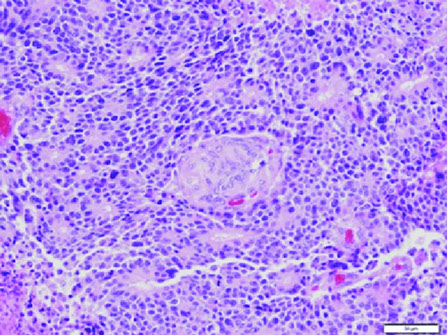

Micro: Characterized by reactive lymphoid follicles

Follicular pancreatitis [2]